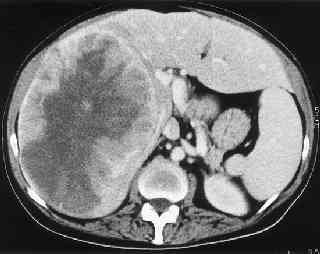

CT_liver_met.jpg (9324 bytes)

Palliation of hepatic metastasis.